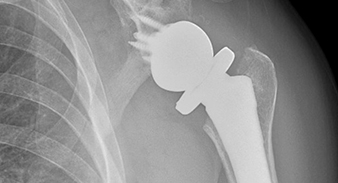

UAB physicians will provide multiple services to Lawson State athletes, including comprehensive musculoskeletal care such as surgical and non-operative treatments...